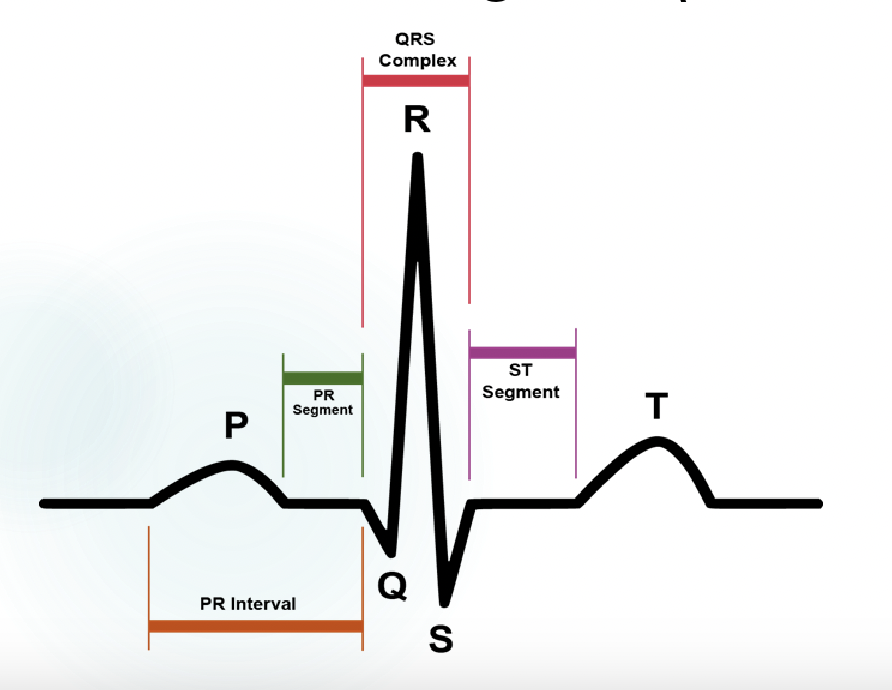

explain what is happening at P, QRS, and T

-p wave: atrial contraction

-QRS complex: ventricular contraction

T wave: ventricular relaxation